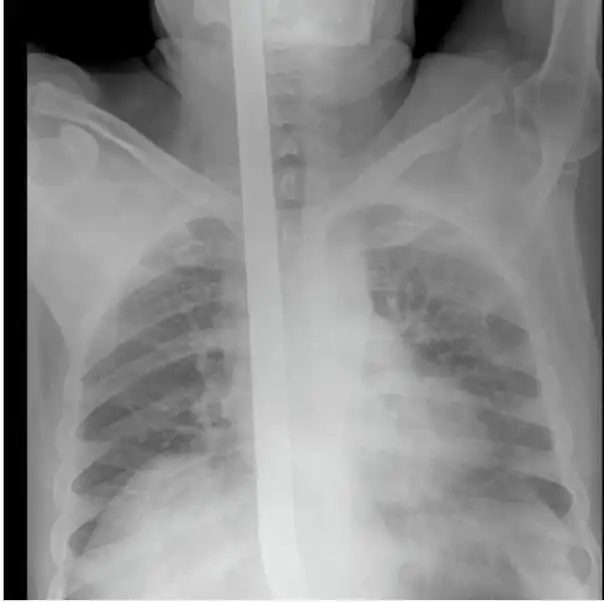

Мужчина упал на лом не повредив жизненно важных органов, говорят после операции выписан в удовлетворительном состоянии домой.

Счастливчик 80 уровня, на снимках и правда видно ни мозг, ни глотку не повредил, везунчик.

Тоже долго башку ломал, пока не дошло - на второй фотке они уже извлеченный лом сверху на простыню положили